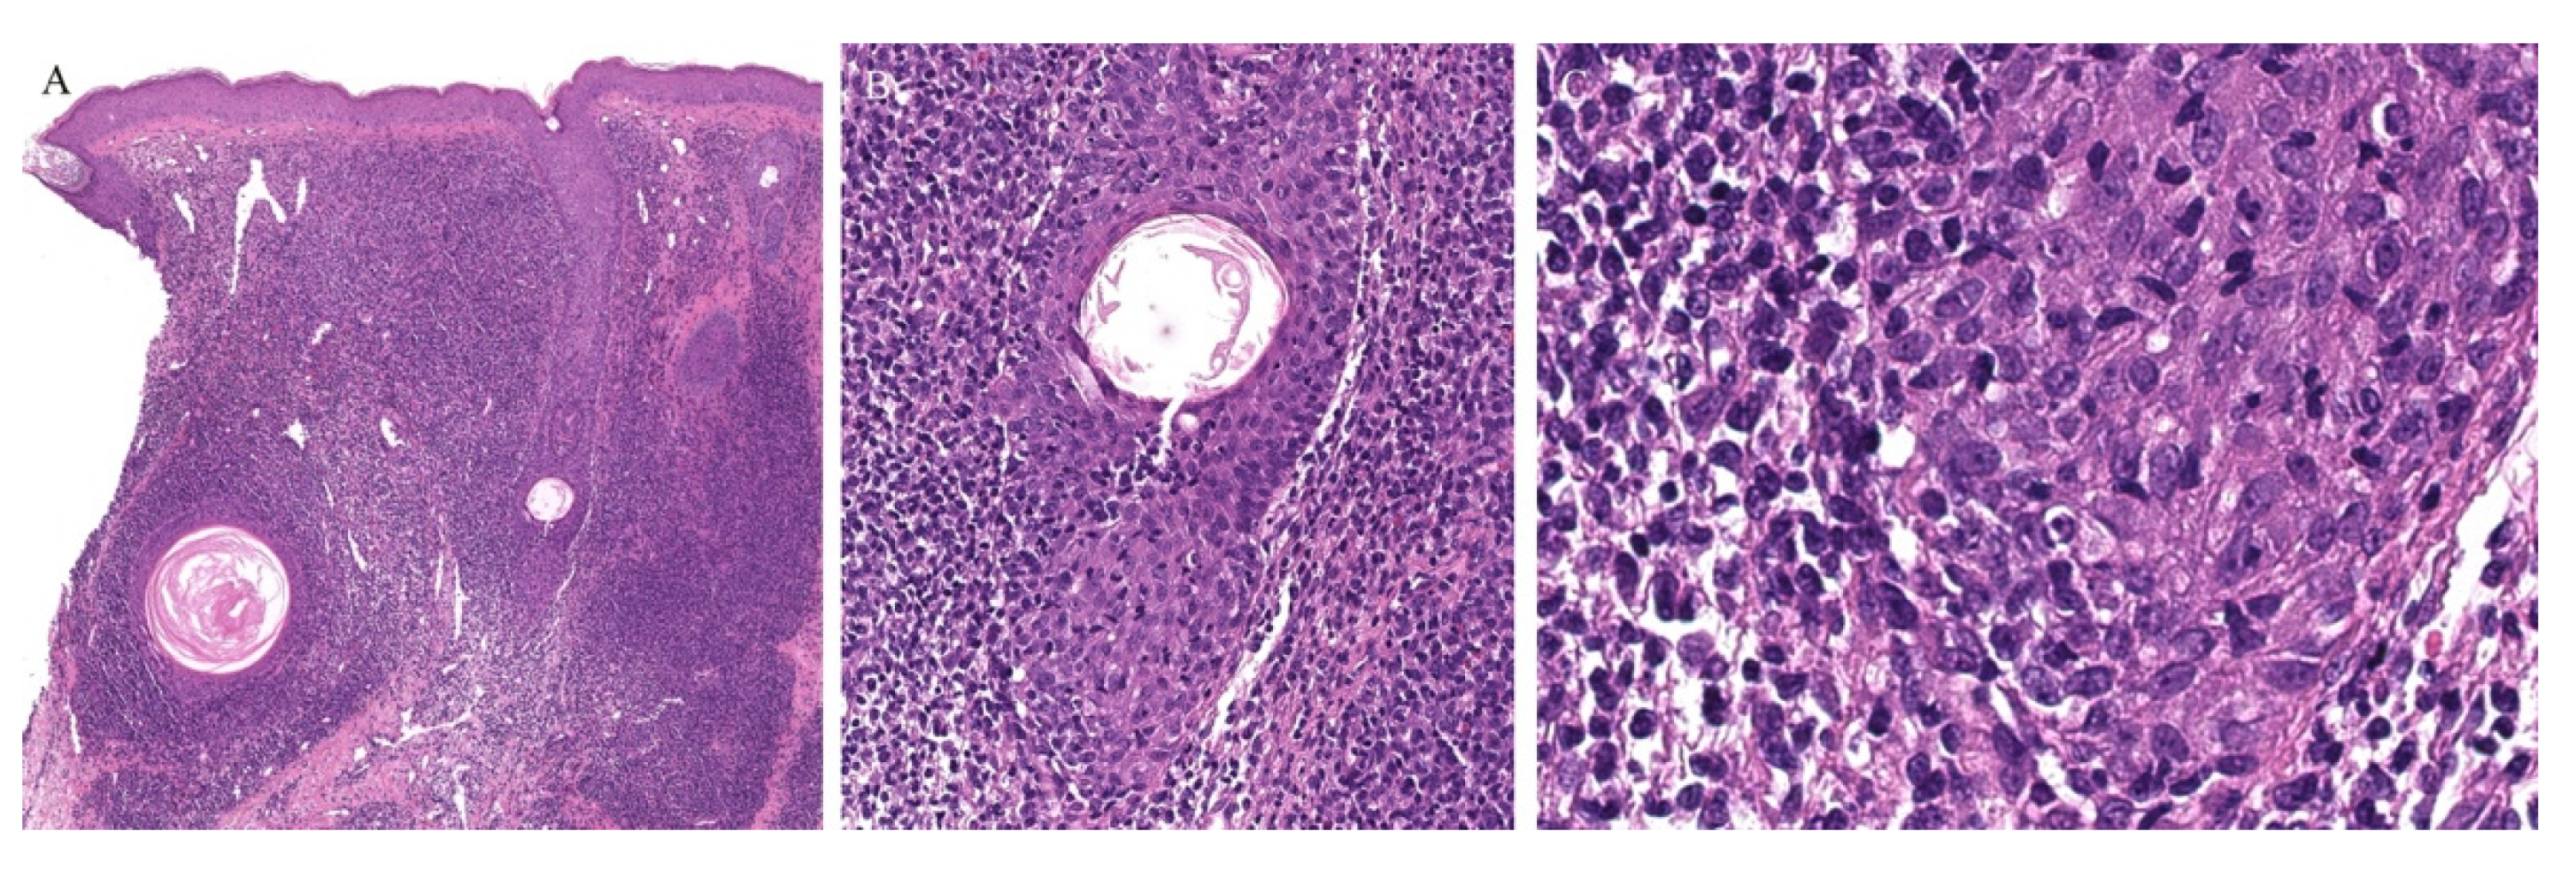

Appendageal involvement has been described. A perifollicular lymphohistiocytic inflammation has been observed in some cases of LN (Figure 3) [18,19]. In addition, a specific clinical variant of LN has been described whereby the papules had a spinous follicular appearance. On histopathology, in addition to the classical LN findings, a granulomatous infiltrate around hair follicles was noted [20,21,22]. The presence of these perifollicular granulomas led authors to emphasize that this clinical variant may be misread as lichen scrofulosorum [20].

Figure 3.

(A–C) Lichen nitidus with follicular involvement (the inset in Figure A shows a deeper section of the same case with more characteristic lichen nitidus changes).

Perieccrine inflammation has also been reported in cases of LN. A lymphocytic eccrine hidradenitis was observed in histopathological specimens of LN, not unlike perieccrine findings seen in lichen striatus [19].